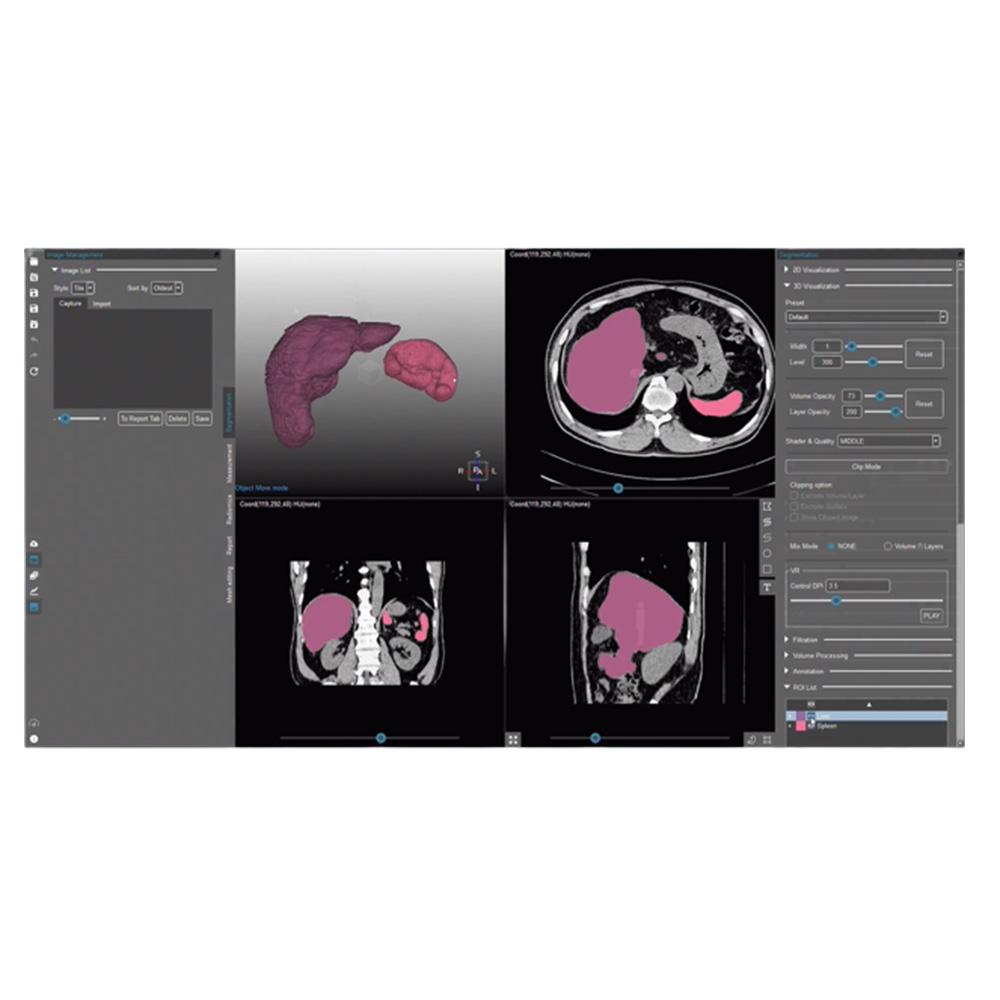

MEDIP PRO is a comprehensive software that processes medical images, enabling image analysis, 3-dimensional construction, modeling, and design with its automatic artificial intelligence (AI) segmentation technology at its core.

MEDIP PRO is equipped with One-Click Segmentation, which helps auto-segmentation

and extracts virtually all human body components in medical images (CT and MR) including patients’ organs and pathologic lesions.

and extracts virtually all human body components in medical images (CT and MR) including patients’ organs and pathologic lesions.

Our technology detects body components including but not limited to lesions from medical images using AI technology and extract quantitative data such as volume and area using our accurate and precise segmentation analysis. This is core technology that sets the basis for the realization of precision medicine by enabling the prediction of the possibility of disease occurrence and monitoring of the patient progress. Based on medical images, we give shape to anatomical digital twin extending our product line to include products for surgical simulation, training, education, as well as patient consultation and diagnosis. Our digital twin expands to the metaverse, a 3D virtual world, enabling medical services and medical education without constraints in time and space.